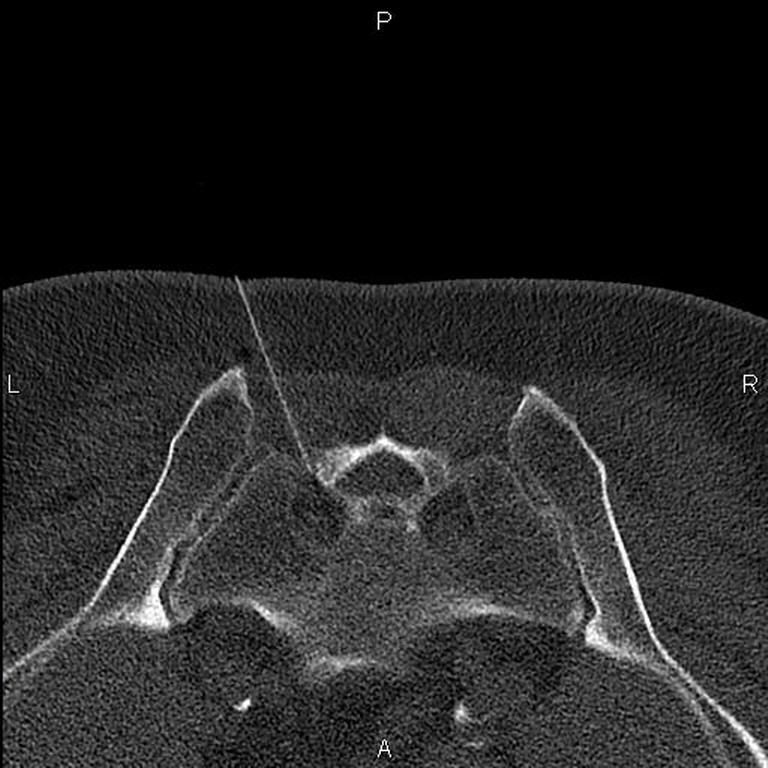

Leiden Sie unter akuten oder chronischen Rückenschmerzen? Die CT-gesteuerte Schmerztherapie (Selbstzahlerleistung) bietet eine zielgenaue und effektive Möglichkeit, aktivierte Gelenkarthrosen oder gereizte Nerven gezielt zu behandeln. Mithilfe der modernen CT-Bildgebung können Schmerzmittel und Cortison präzise an die betroffenen Stellen injiziert werden, wodurch eine schnelle und langanhaltende Linderung der Schmerzen erreicht wird. Unsere Schmerztherapien umfassen Facettenblockaden, ISG-Blockaden und periradikuläre Therapien (PRTs).